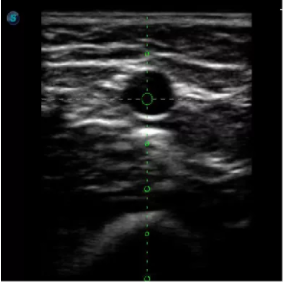

4  置管專用探頭

實(shí)時(shí)觀察穿刺針進(jìn)入血管的全過程,方便操作及較短的穿刺路徑,智能進(jìn)針尺寸提示,讓置管工作更加輕松,高效。

不同進(jìn)針路徑